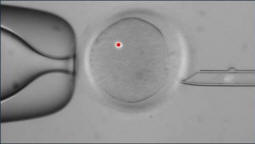

Създадоха учени от университета в Орегон Health & Sciences ембриони с гени от един мъж и две жени. По този начин появата на деца, които имат не две, а три родителят.

Снимки от отворени източници Тази технология може да се промени социална структура на съвременното общество, даваща възможност “пълноценно функциониращи” семейства на няколко съпрузи. Между другото, в самите САЩ и в някои други страни в момента Правят се корекции в законодателството, които позволяват такова възможност. Например в Бразилия тази година за първи път регистрира брака на трима души и в Калифорния законно Дете може да бъде повече от двама родители. Но основното е нова техника може да помогне да се предотврати предаването на наследствено нелечимо заболявания. Преди това експерти от Великобритания се опитаха да повторят опита. Учените направиха изявление, че са създали дете, което има три родителят. Но подобно твърдение беше неоснователно. Женска ДНК възлиза на не повече от 1% в генния набор. Освен това тази ДНК не е от клетъчно ядро, беше част от митохондриите. Генетик болестта, която са се опитали да излекуват, се предава чрез майката линии в митохондриалната ДНК. В света в 1 случай от 5 хиляди има дете с генетично разстройство, което се понася митохондриална ДНК. Поради това децата могат да бъдат слепи, да страдат от епилепсия или бъбречна недостатъчност. Дарението на ДНК дава шанс такива деца се раждат здрави.

Учени от здравния университет в Орегон изследвали ядрената ДНК, което дава възможност да се продължи по този въпрос. Ако опит оправдава се, тогава в бъдеще учените ще заменят гените, които носят болестта в яйцето до “здравословно” и след това ще го пренесе оплождане от мъжки репродуктивни клетки. Засега по етичен причините, поради които не планират да отглеждат бебе от ембриона, като това предизвиква много спорове от страна на обществеността.